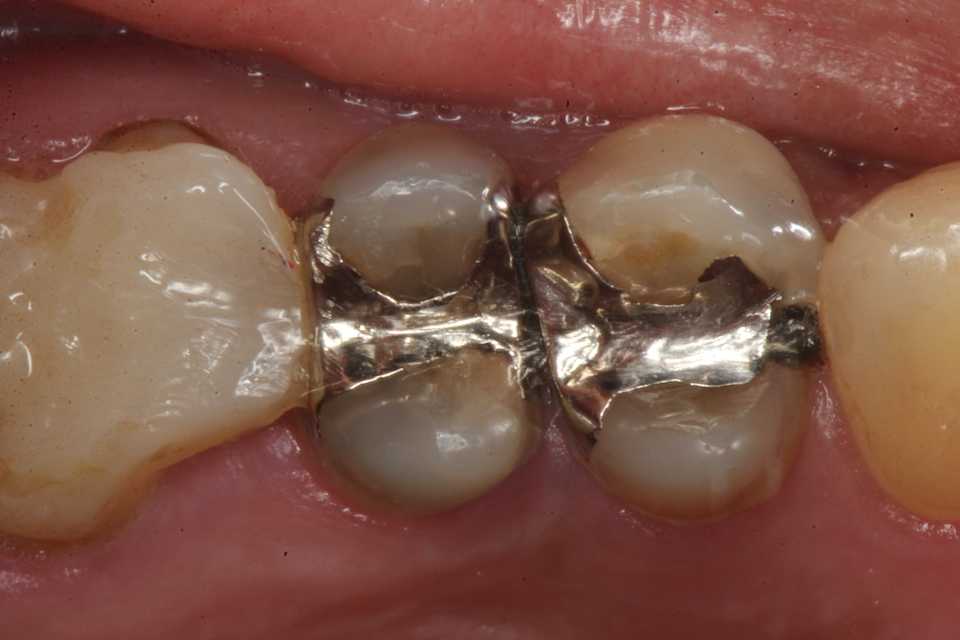

40代女性、左上5、自発痛+この方も痛くならないと来ない人。痛みが出ている歯は不可逆性の歯髄炎とか言って、治らないので通常は神経を取って被せるとか回数がかかり面倒な治療をするということになるのだが、僕にはそんな体力も、暇もない、お金も要らないとなれば、1回で終わるCRでの再建をするしかない。露髄(黄色矢印)しているのだけれど、3MIX+α-TCPで直覆すればなんにも症状は出ない。その場で痛みは消え失せる。露髄しているとか痛みが出ている歯は神経を取らないとだめ、というのは抗菌剤のなかった50年以上前の話のはずなのだが、なぜか今もやっている。多分そうしないと間がもたないとか、儲からないとか、CR再建の技術がないとか、そもそも歯学部で習っていないとか、大人の事情があるのだろうと思う。この方はデンタルフロスとか使う様な方ではないので、隣接面にフロスが通る様にはしていない。僕が使っているボンディング材はこちら。α-TCPの50%クエン酸練り。この上からCRダイレクトボンディングでカバーする。3MIXの作り方はこちら。α-TCPの入手法はこちらでは時系列でどうぞ中身(象牙質)は無い。イオン化傾向は象牙質>エナメル質>金属の順だ。この順序で溶ける。これを異種金属接触腐食という。3MIX+α-TCP1次CR次回は手前側の4番の予定